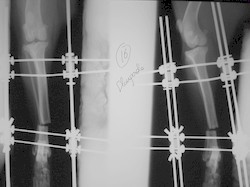

PRÁCTICAS CURSO DE FIJACIÓN EXTERNA PERFECCIONAMIENTO.

Elongacion.